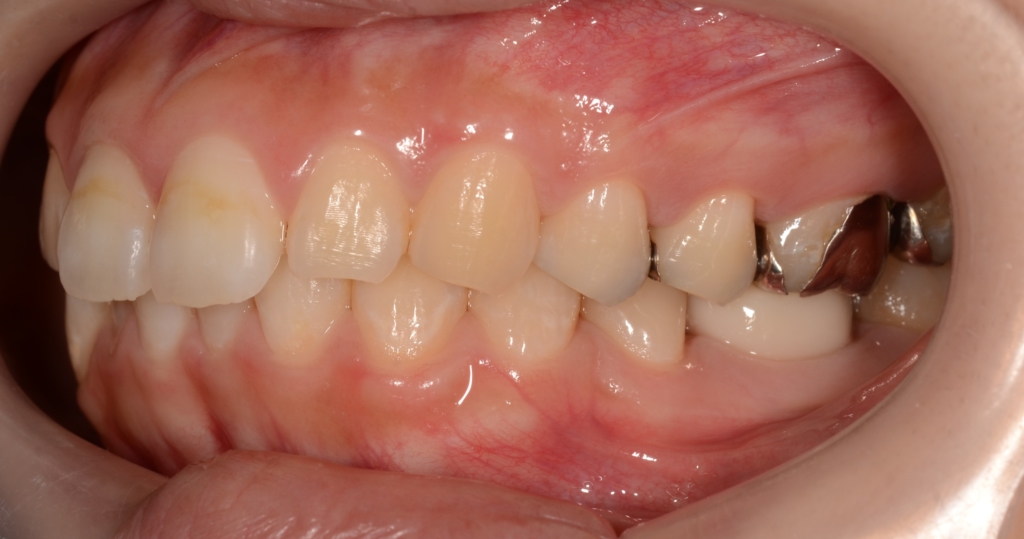

治療に伴う歯肉の変化をお見せしましょう。

上段が圧下治療開始時点、下段が圧下治療終了後 になります。

アンカースクリューは動きませんから、上記の写真を見れば、圧下治療に伴い前歯が周りの歯肉ごと押し込まれて歯肉の見え方が狭くなったことが一目瞭然で分かると思います。